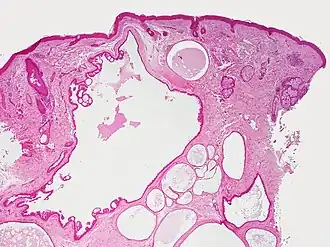

El hidrocistoma (también conocido como cistoadenoma,[1] quiste de las glándulas de Moll,[1] o quiste sudorífero[1]) es un adenoma de las glándulas sudoríparas.[2] : 787

Los hidrocistomas son quistes de los conductos del sudor, generalmente en los párpados.[3] : 664 No son tumores.

Generalmente surgen de las glándulas apocrinas. También se les llaman quistes de Moll o quistes sudoríferos. Puede haber un tipo de hidroadenoma que surge de las glándulas ecrinas, pero estos son poco comunes.